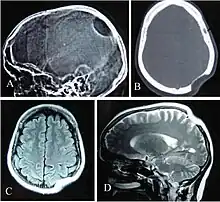

Gorham's disease involving the left parietal bone: X-ray of the skull lateral view (A) showing a osteolytic area in left parietal region. CT scan bony window (B), MRI T1W Axial (C) and T2W Sagittal (D) revealing skull defect with normal brain parenchyma.

Often, Gorham's disease is not recognized until a fracture occurs, with subsequent improper bone healing. The diagnosis essentially is one of exclusion and must be based on combined clinical, radiological, and histopathological findings.[7] X-rays, CT scans, MRIs, ultrasounds, and nuclear medicine (bone scans) are all important tools in the diagnostic workup and surgical planning, but none has the ability alone to produce a definitive diagnosis. Surgical biopsy with histological identification of the vascular or lymphatic proliferation within a generous section of the affected bone is an essential component in the diagnostic process.[7][8][11]